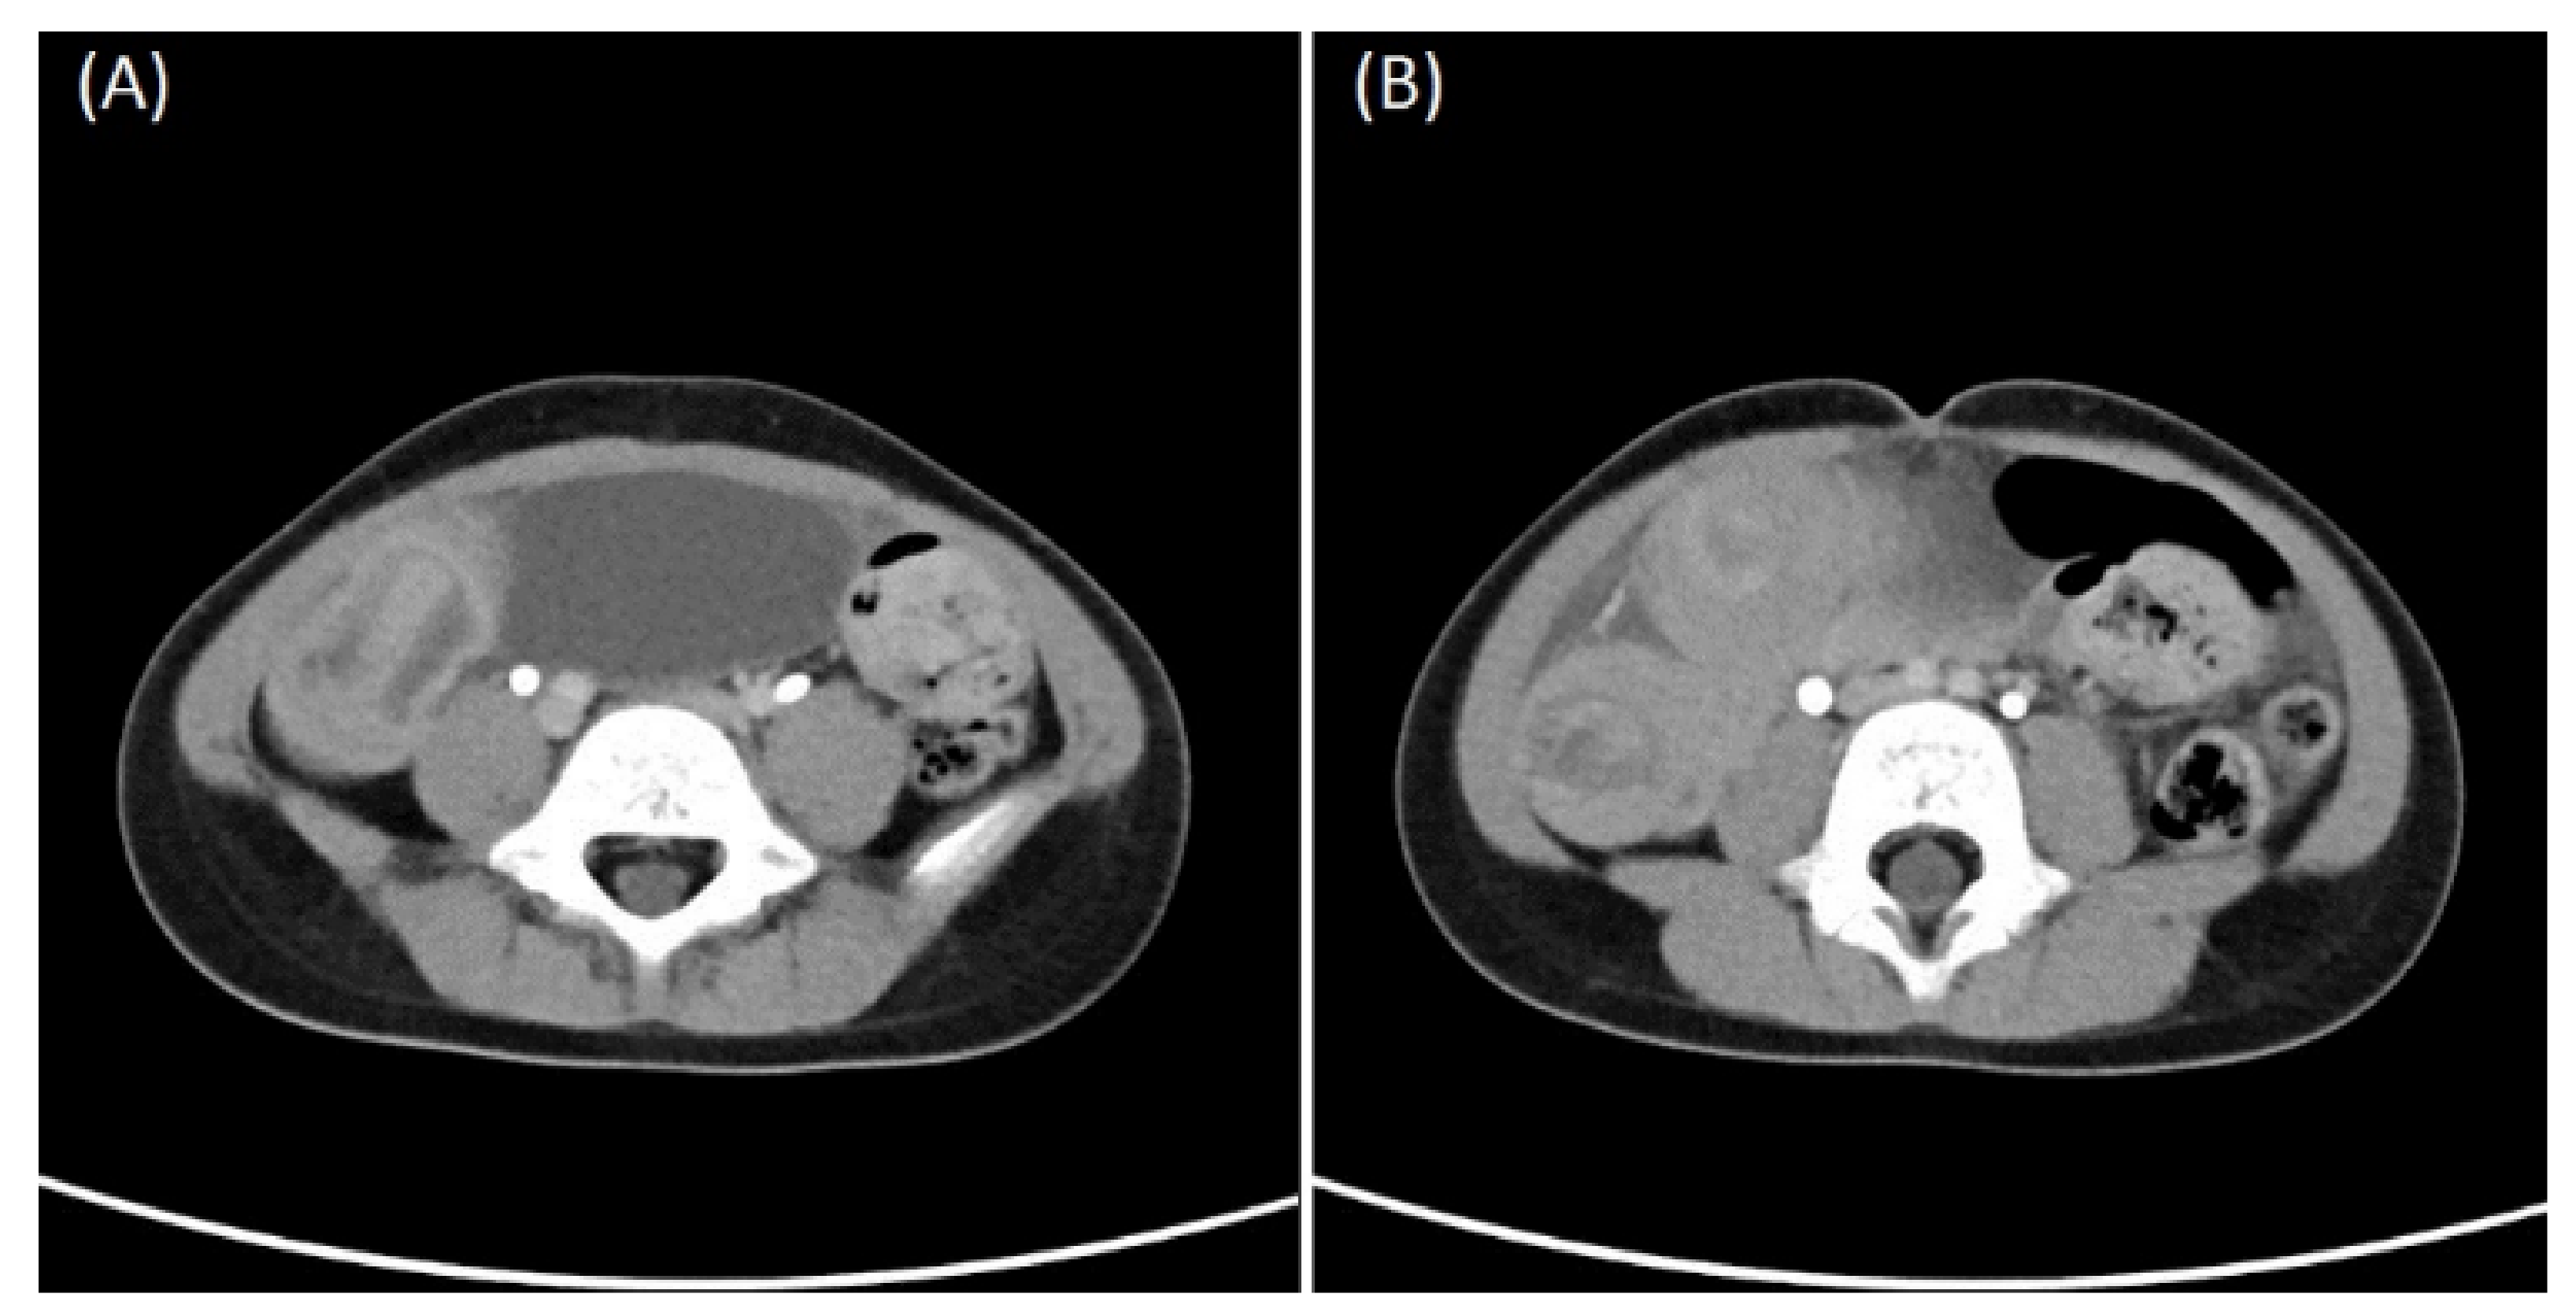

| One month prior to this admission | A medical center | Computed tomography (CT) suspected intussusception but upper gastrointestinal series showed negative finding. Incompletely obstructing intussusception was suspected again. |